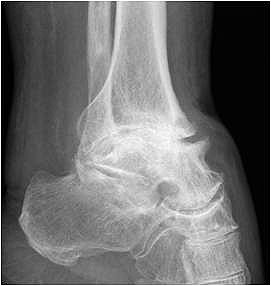

• Revision einer gescheiterten Fusion des OSG/ USG (Abbildung 3, Abbildung 4).

• Pseudarthrosen (Abbildung 5, Abbildung 6).